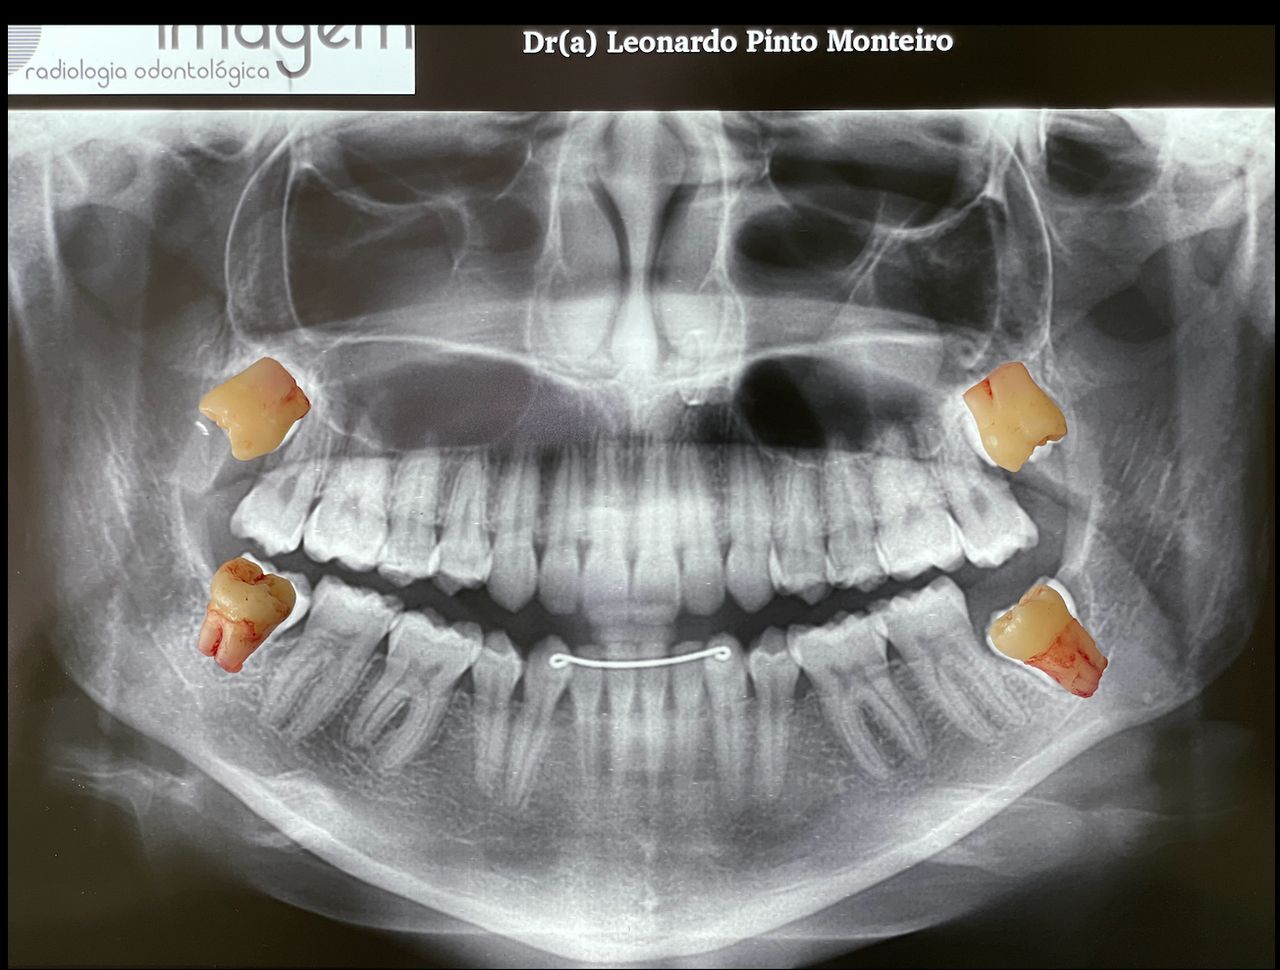

* Análise de Imagens de Alta Complexidade: Como cirurgião, interpreto Ressonâncias Magnéticas e Tomografias buscando detalhes que muitas vezes passam despercebidos em exames de rotina.